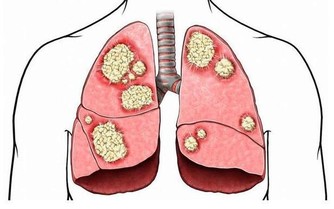

當動脈血管堵塞75%以上,血流量過少時,胸悶、氣短、頭暈、頭痛等不適就會出現,更嚴重還會誘發腦卒中、心肌梗死等疾病。